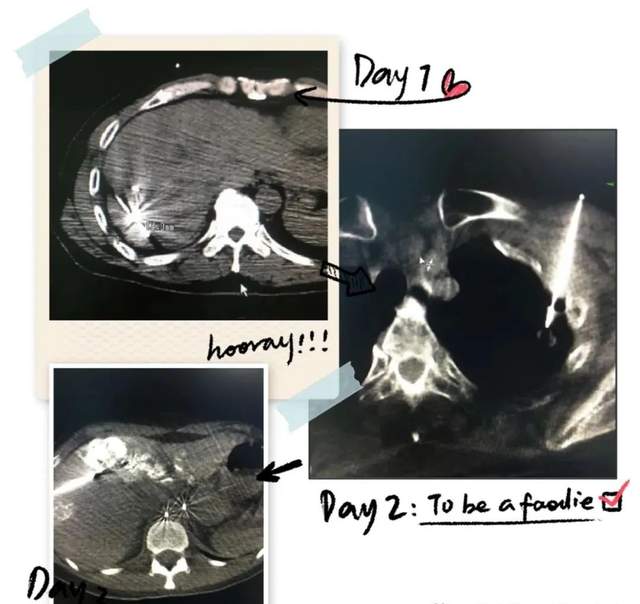

脑转移放疗后病灶几乎消失

乳腺癌术后辅助放疗

保乳术后放疗

股骨头转移放疗